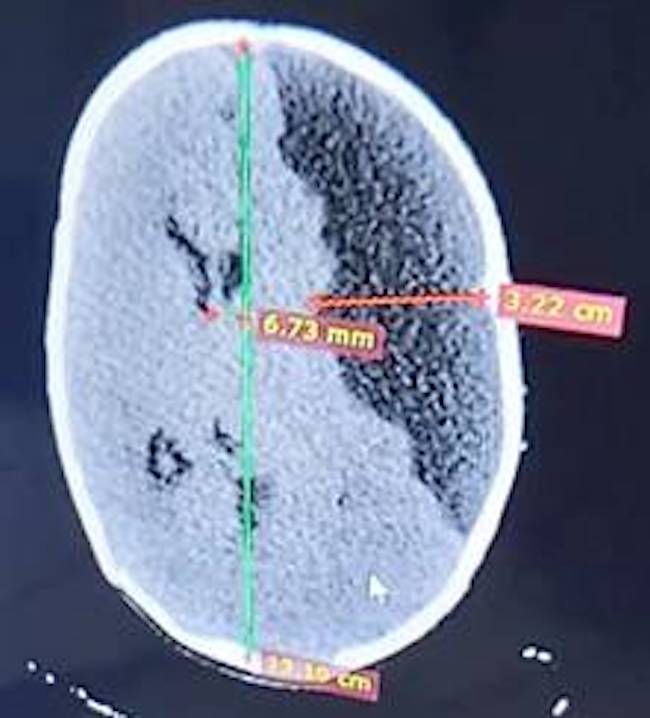

Se presenta el caso clínico de un lactante de 47 días de nacido, blanco, con 4,8 kg de peso, quien fue atendido en el Cuerpo de Guardia de Pediatría del Hospital Provincial General Docente Antonio Luaces Iraola de Ciego de Ávila, pues según manifestó su mamá, en consulta de puericultura le encontraron la “cabeza grande” (aumento de la circunferencia cefálica). Además, se encontraba irritable y agitado. Se realizó interconsulta con la especialidad de neurocirugía y se decidió ejecutar tomografía axial computarizada (TAC), así como ultrasonido transfontanelar (fig.). Dichos exámenes mostraron signos de hipertensión endocraneana (HTE) en fase de descompensación, secundaria a colección del espacio subdural del lado izquierdo. No fue posible el traslado del paciente al Hospital Pediátrico de Camagüey para realizar el tratamiento quirúrgico, el cual se decidió realizar por primera vez en la provincia de Ciego de Ávila, con el acompañamiento de especialistas en neurocirugía infantil y anestesiología de la institución agramontina. El procedimiento fue ejecutado sin contratiempos y la evacuación del higroma subdural se realizó guiada por ultrasonido.

El proceso de recuperación fue favorable en las primeras 36 horas. Luego, comenzó a convulsionar y apareció nuevamente el deterioro neurológico, que obligó a repetir la TAC de cráneo, en la cual se observó nuevamente, un higrohematoma contralateral. Debido a la urgencia se decidió reintervenir, esta vez por un equipo de especialistas avileños.